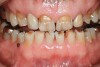

Figure 14  Bruxism triad in a young adult. The pathologic wear, once limited to the anterior teeth, is beginning to appear on the posteriors as guidance is lost. Patient reported sleep issues that became exacerbated with pregnancy. GERD was intermittent until pregnancy then it increased.

Figure 14